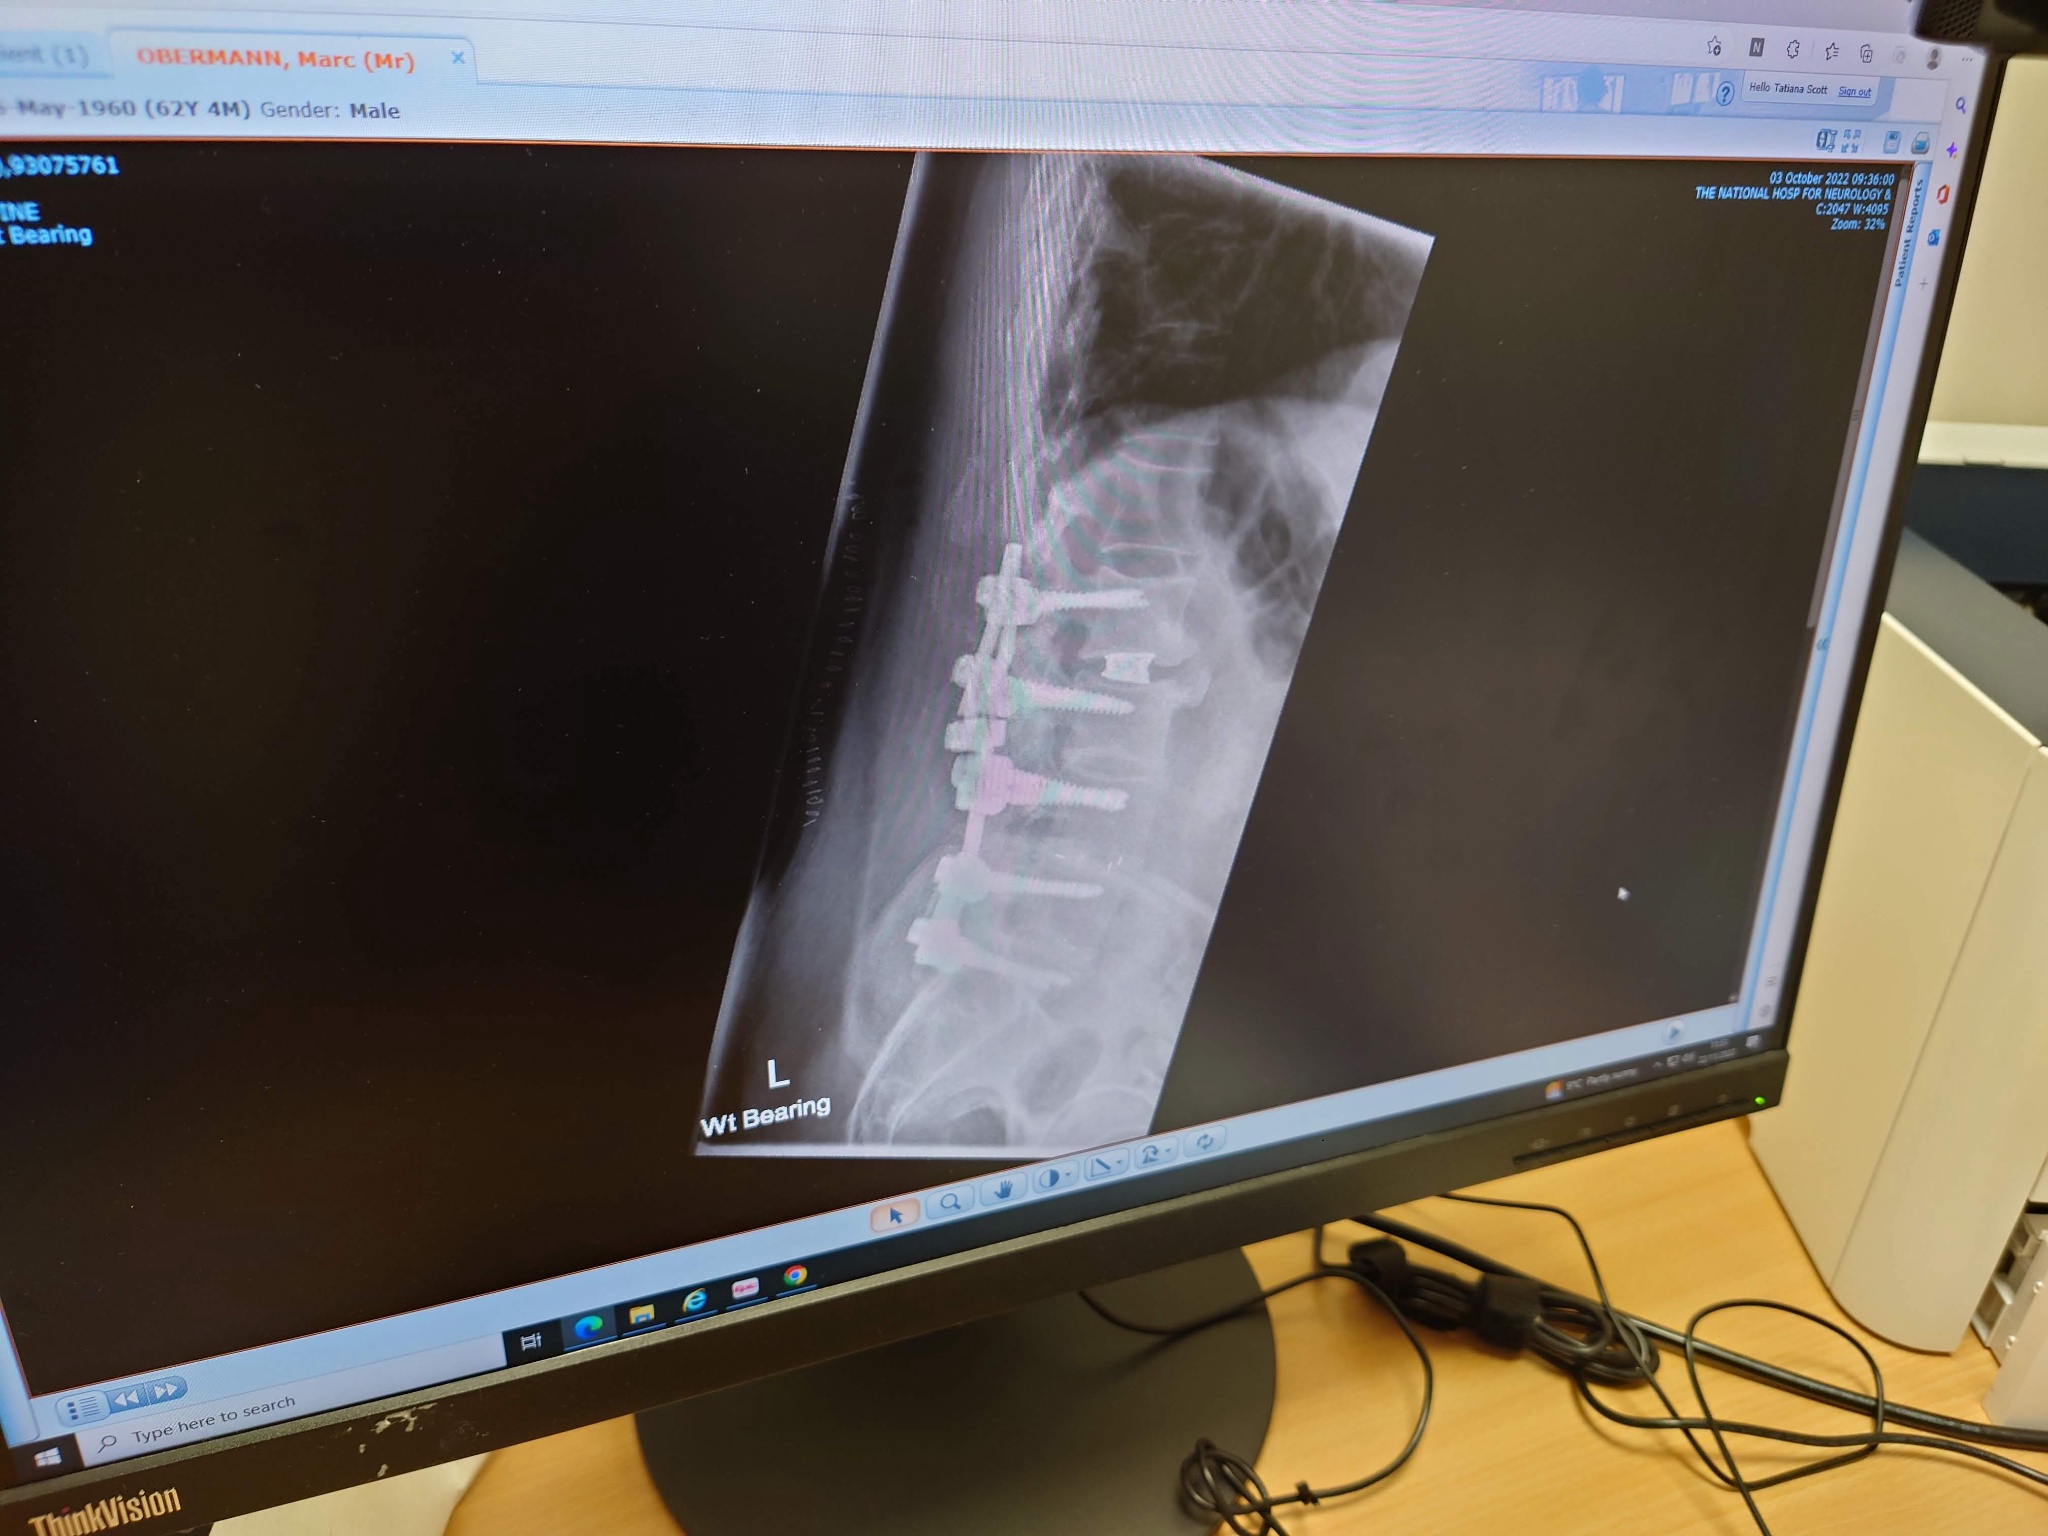

At this point after 25 years and multiple complex spinal surgeries resulting in a fusion of my spine from L2-S1 and having had every pain root and nerve injection known to man. All that has done little to help with my constant lower back pain that is at an 8 on the pain scale at best and 10 when really bad this really is my last option more or less. So here goes nothing I have a consultation soon so only time will tell if it works for me or not. As we all like a pretty picture here is an X-ray of my back after my last surgery in 2022.